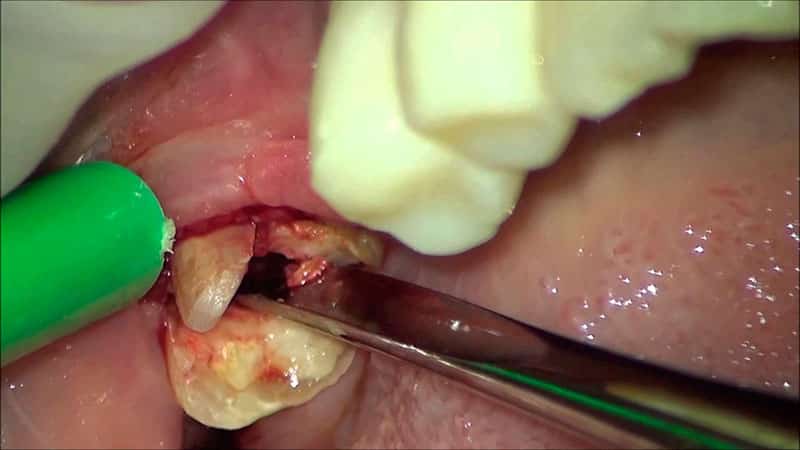

Как удаляют «мудрые» моляры

Сложное удаление зуба мудрости